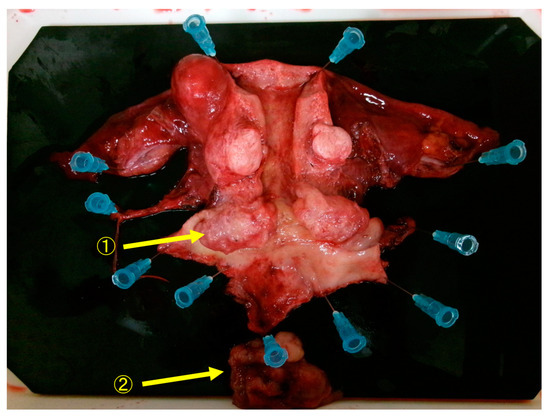

Figure 4.

Macroscopic findings of the resected specimen showed that the resection margins between the tumor and the parametria were negative, and the resection was diagnosed as complete. ① Cervical tumor. ② Tumor that has fallen off from the cervical tumor.